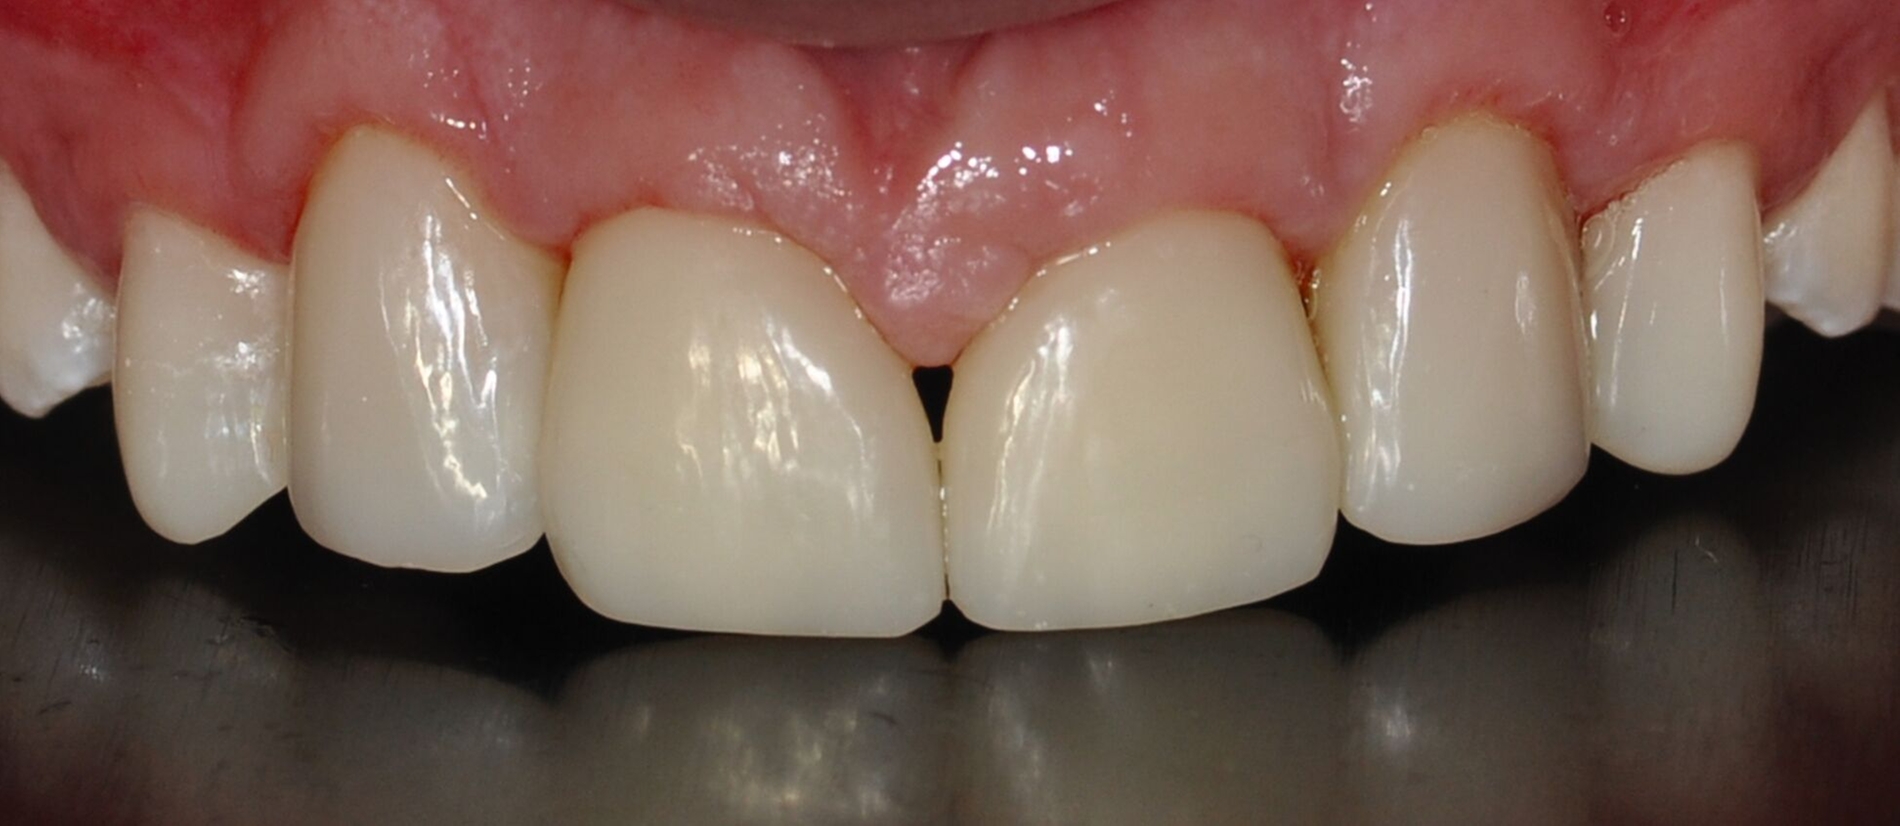

Nach sechs Monaten zeigen sich stabile restaurative und parodontale Verhältnisse mit Sondierungstiefen von maximal 3 mm. Der Patient befindet sich in der regelmäßigen Betreuung seines Hauszahnarztes und nimmt dort halbjährliche Vorsorgeuntersuchungen sowie Professionelle Zahnreinigungen wahr. Alio loco wurde der seitliche Kreuzbiss zwischenzeitlich nochmals kieferorthopädisch korrigiert, wenn auch das Behandlungsergebnis aufgrund ausbleibender Adhärenz weiterhin kompromittiert erscheint. Zur Sicherung des Behandlungsergebnisses wurden Retentionsschienen für den Ober- und Unterkiefer angefertigt. Im Unterkiefer wurde zusätzlich ein festsitzender Retainer eingegliedert.

Auch bei einer Kontrolluntersuchung drei Jahre nach restaurativer Therapie sind die Versorgungen in situ, intakt, und das Parodontium zeigt keine entzündlichen Veränderungen. Trotz Anfertigung der Retentionsschienen fällt ein beginnendes Diastema mediale auf (Abbildung 4). Der Patient gibt auf Nachfrage an, die Schienen nicht regelmäßig getragen zu haben. Ihm wird die Möglichkeit eines Diastemaschlusses durch eine erneute Zahnformkorrektur angeboten. Da ihn die entstandene Lücke jedoch subjektiv nicht stört, entscheidet er sich zunächst gegen eine restaurative Korrektur.